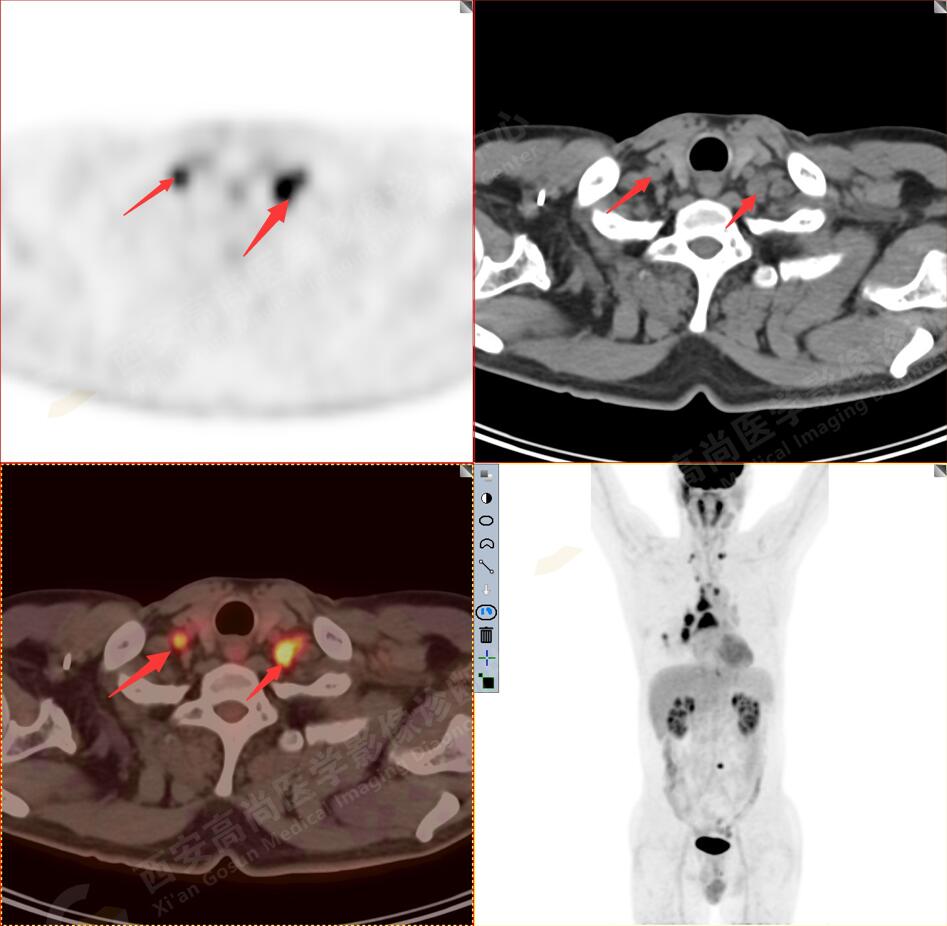

2.以下為全身多發(fā)轉移灶

3.右側肺門、縱隔(1L、1R、3A、4、6、7組)及雙側鎖骨上多發(fā)腫大淋巴結,呈不同程度FDG代謝異常增高,考慮為淋巴結轉移。